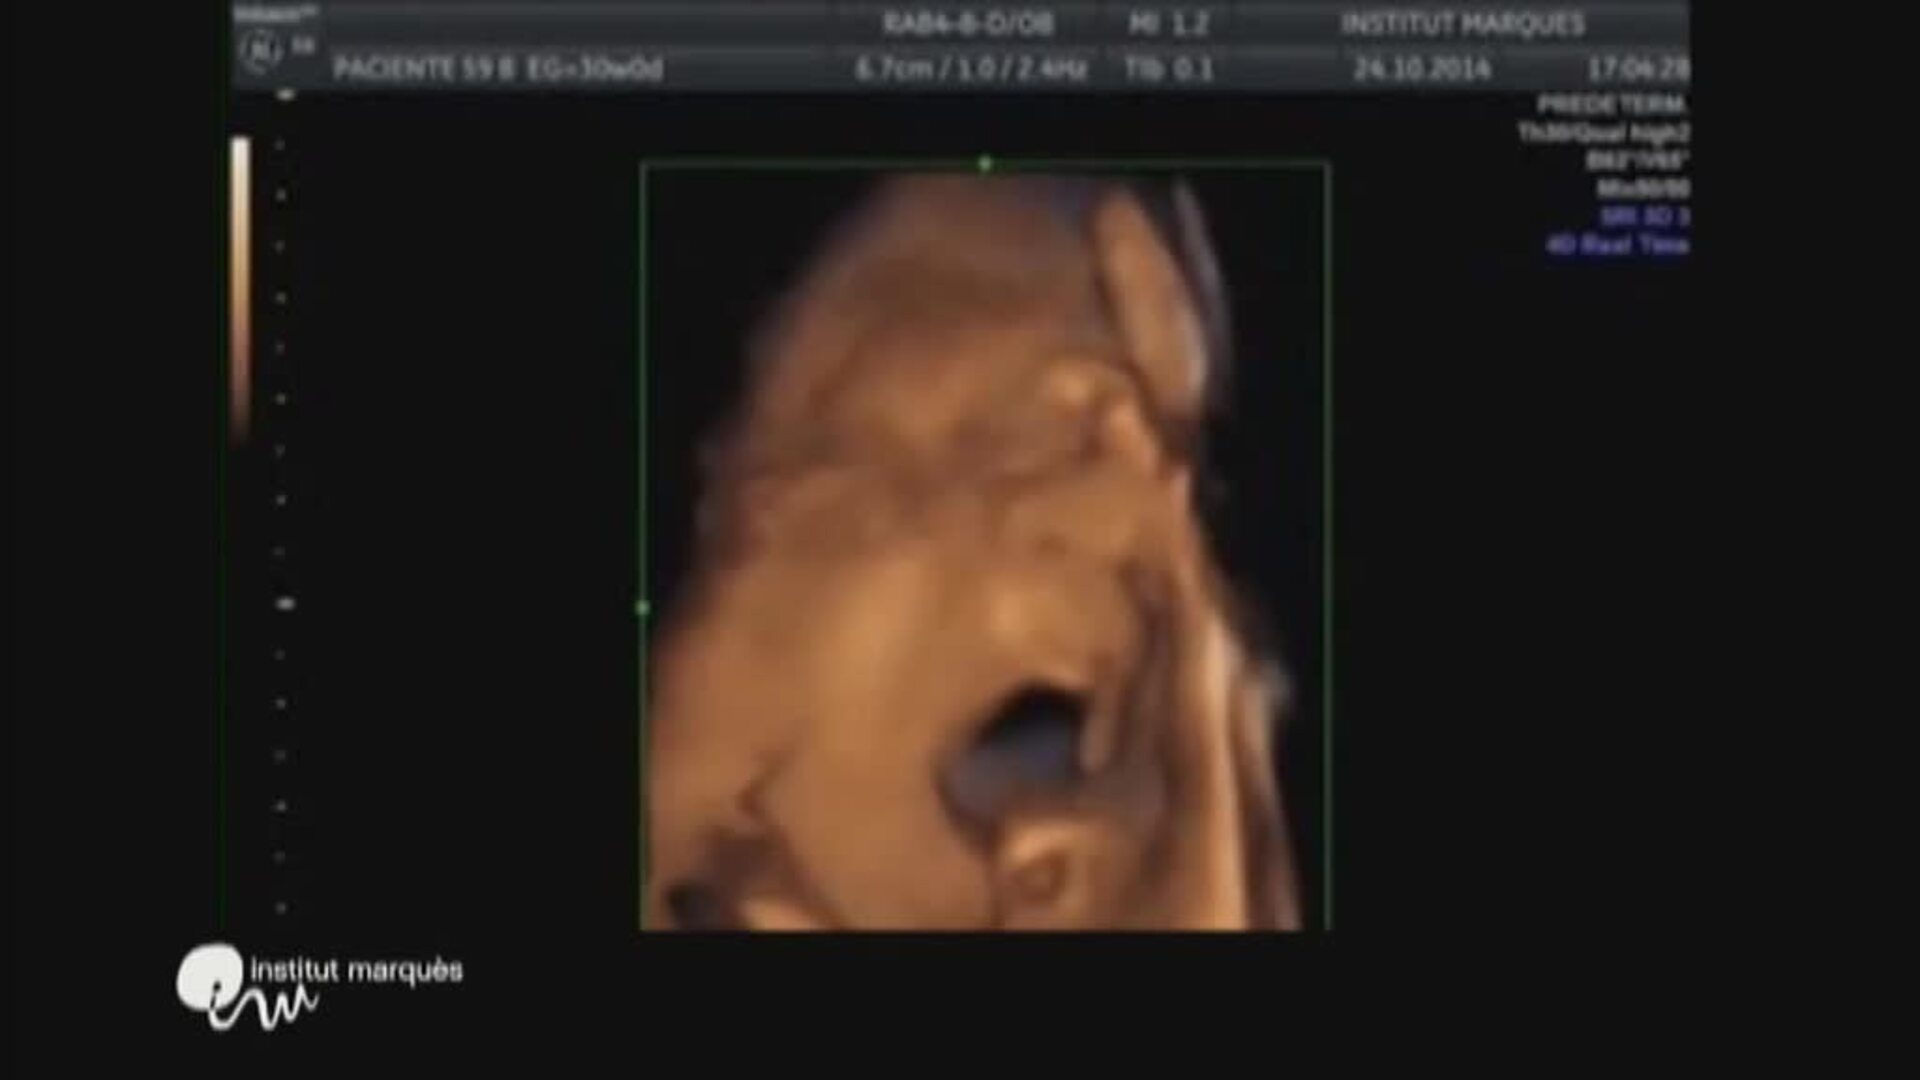

Un estudio de la revista Nature aporta nuevos datos sobre los beneficios de un parto por vía vaginal. Los nacidos por esta vía reciben de sus madres un torrente de bacterias que son claves para, por ejemplo, funciones digestivas. Sin embargo, los nacidos por cesárea ... presentan una mayor tendencia a sufrir asma, alergias u obesidad. La Organización Mundial de la Salud recomienda que el nivel de cesáreas no debe superar el 15%, no obstante, en España se practica en más del 25% de los partos.